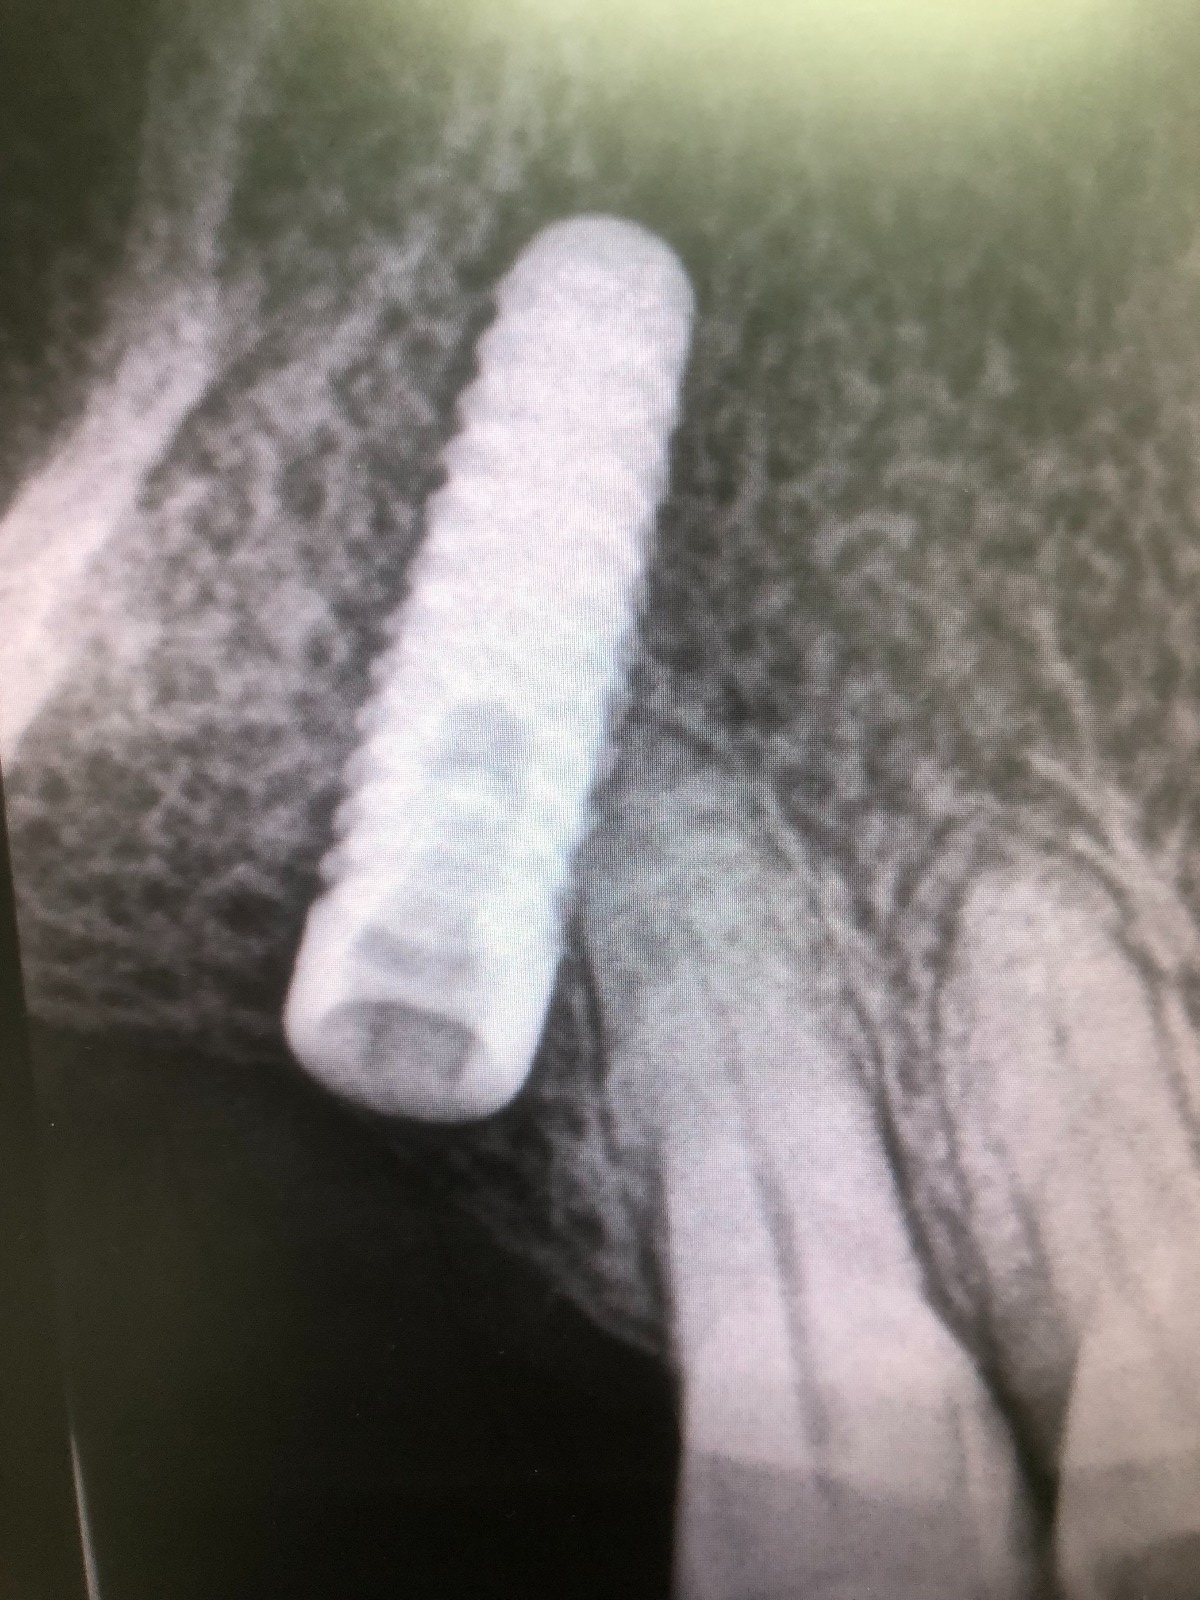

Como hemos comentado es un molar, es decir, una pieza dental en la zona posterior de la boca y con una posición del implante muy inclinada para poder esquivar el seno maxilar, lo cual dificulta mucho el trabajo.

En realidad, lo más notorio de este caso es el uso por primera vez de un tornillo pasante mucho más sofisticado fabricado y distribuido por la empresa Suministros ASATIM. Este tornillo pasante es especial porque está fabricado en cromo-cobalto recubierto de nitruro de titanio. Esto le imprime una gran biocompatibilidad. Y también, al ser aleación de cromo-cobalto presenta mucha más resistencia a la fractura que si estuviera fabricado en aleación de titanio. De hecho el límite de elasticidad de la aleación de cromo-cobalto es el doble al límite de elasticidad de la aleación de titanio.